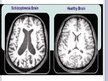

Laboratory tests – blood and urine tests, brain-imaging studies (such as an MRI or a CT scan).